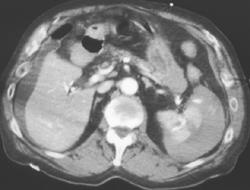

Lymphoma Involves the Spleen